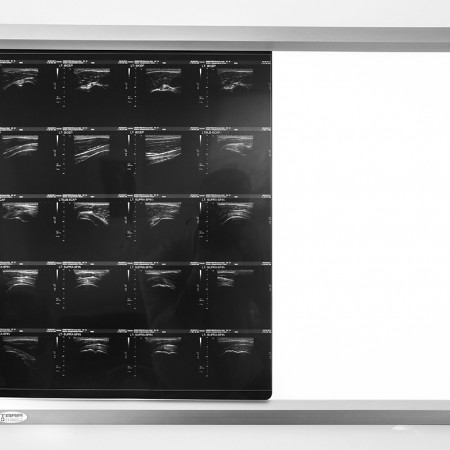

Dr Pendleton will provide a full and rapid diagnostic service and personalised management plan for all rheumatological conditions. Patients will have access to the latest biochemical, immunological and radiological investigations including specialist X-rays, musculoskeletal ultrasound scans and MRI.

Recent Photos